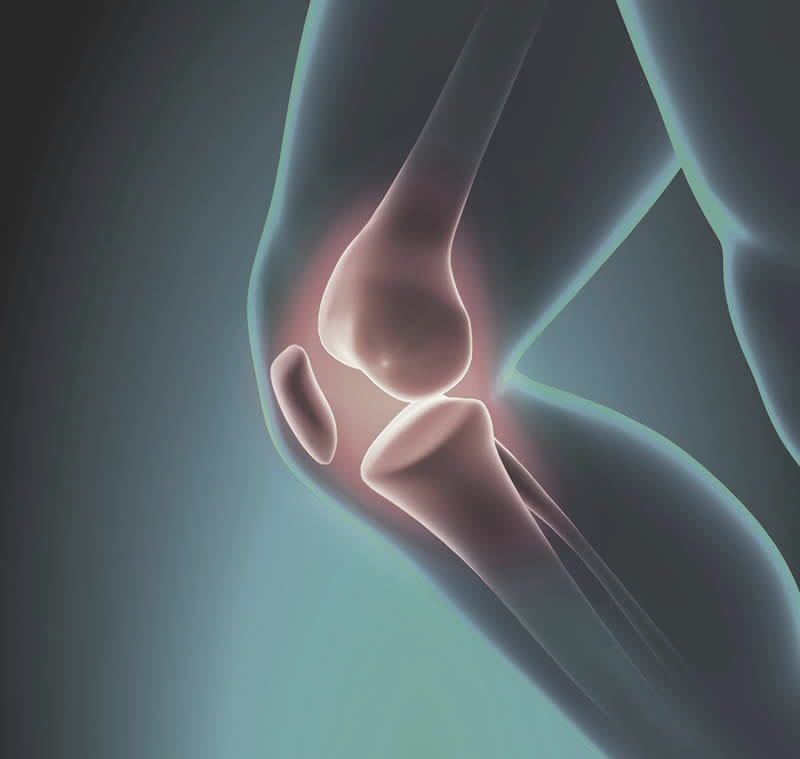

主治項目